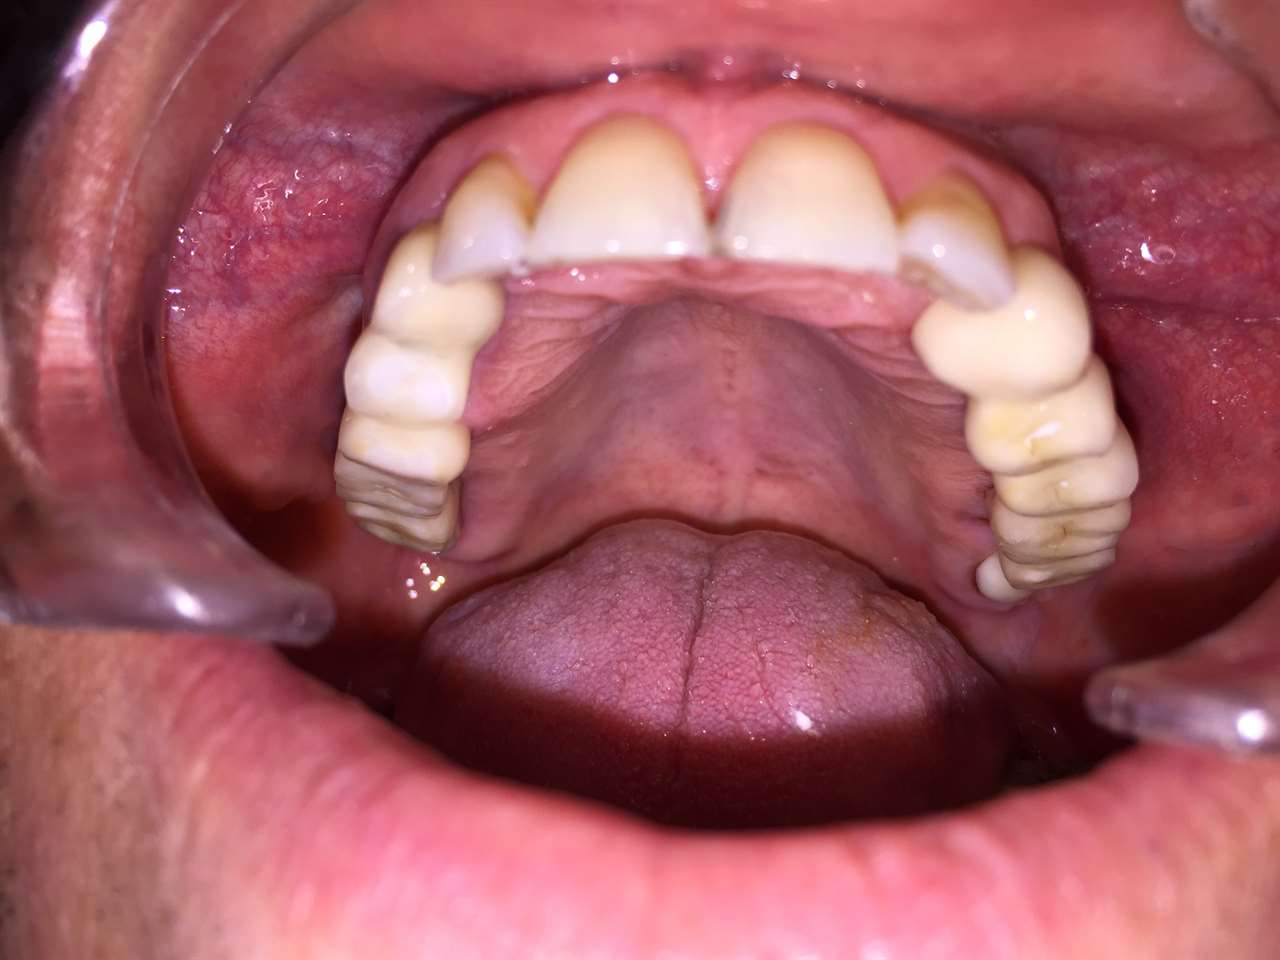

Teljes fogatlanság helyreállítása 2 nap alatt

Teljes fogatlanság helyreállítása 2 nap alatt azonnal terhelhető svájci IHDE implantátumokkal és PMMA műanyag hidakkal. Intraorális szkennerrel vettünk lenyomatot az implantáció után, és erre a digitális mintára készítette el a fogtechnika a hidak digitális tervezését, majd faragta ki műanyagból. Ezt a gyors munkát az azonnal terhelhető implantátumok és a digitális lenyomat, tervezés segítségével tudtuk megcsinálni mindössze 2 nap alatt. Dr. Kelemen Péter és a Symbion Fogtechnika munkája.